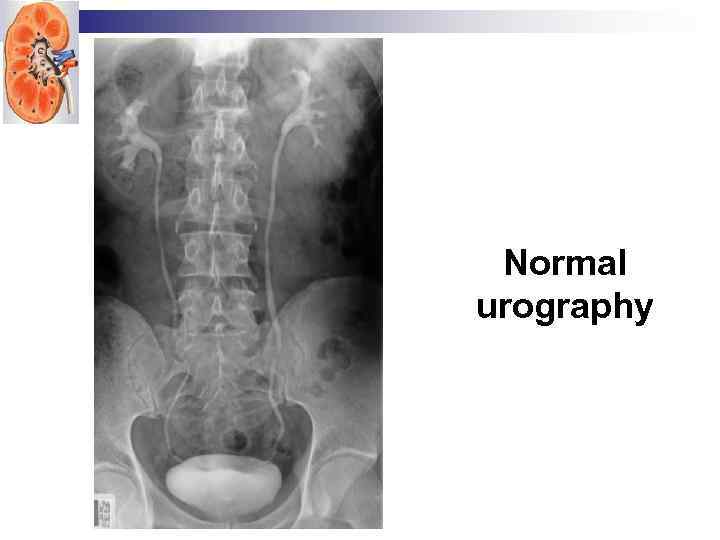

Normal urography

Normal urography